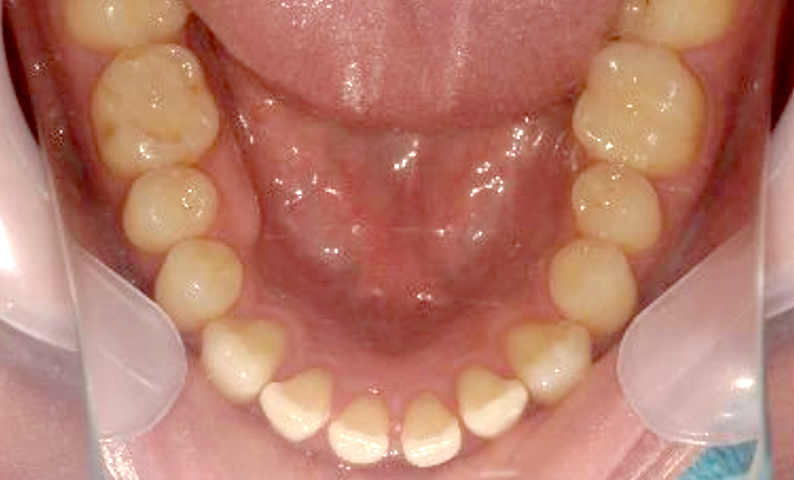

| 治療前 | 治療後 |

|---|---|

|